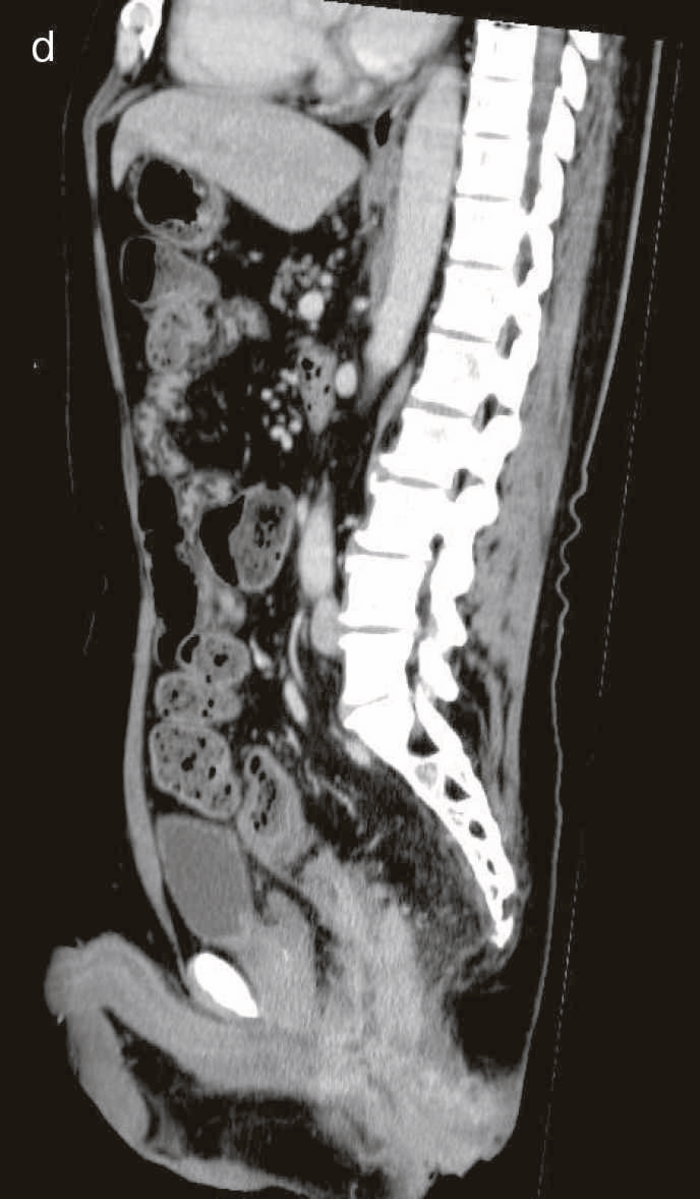

図34 術前CT

術前CTでは回腸末端の壁肥厚を認め,周囲リンパ節の腫大は明らかではなかった。